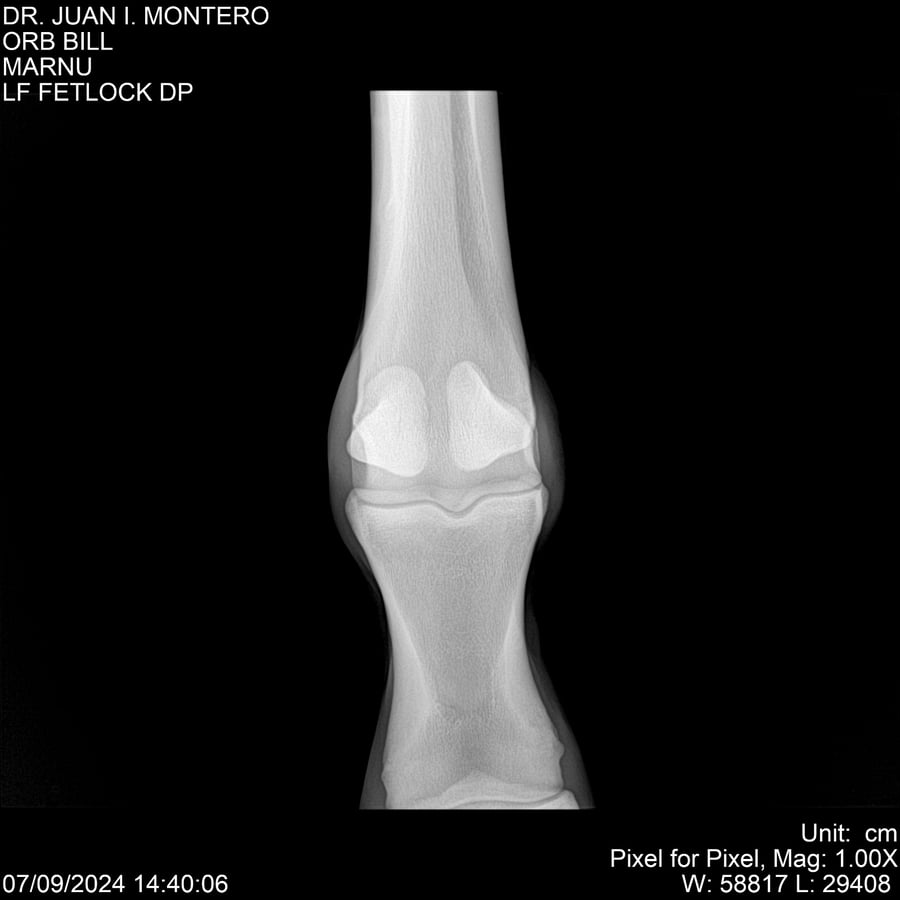

LOTE 7, ORB BILL 🔥 🔥 🔥 Lote Anterior Volver al remate Lote Siguiente Ficha Contacto Montevideo - Ficha del Lote Identificador: #282523 Categoría: Yeguarizos Montevideo - 83 Visualizaciones ClicData Contacto Empresa: Abelenda N. R., Walter Hugo Nombre*: Teléfono* : E-mail* : Mensaje Enviar Registrese gratis Este contenido Exclusivo está disponible sólo para usuarios registrados Ingresar